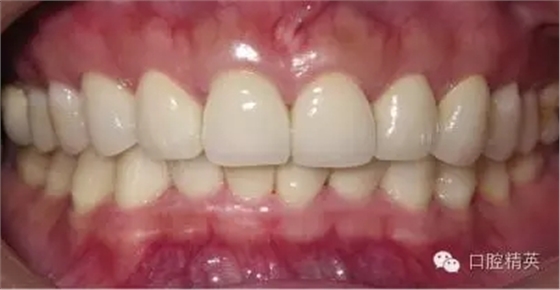

粘固后,對(duì)咬合關(guān)系進(jìn)行初步調(diào)整。三天后,復(fù)查,進(jìn)一步確認(rèn)咬合關(guān)系,必要時(shí)進(jìn)行調(diào)整(見(jiàn)圖12)。

LAVA 全瓷冠強(qiáng)度高,顏色自然,邊緣高度密合,切端可見(jiàn)半透明感,整體效果理想,與修復(fù)前(見(jiàn)圖1)相比取得了醫(yī)患均滿意的效果。